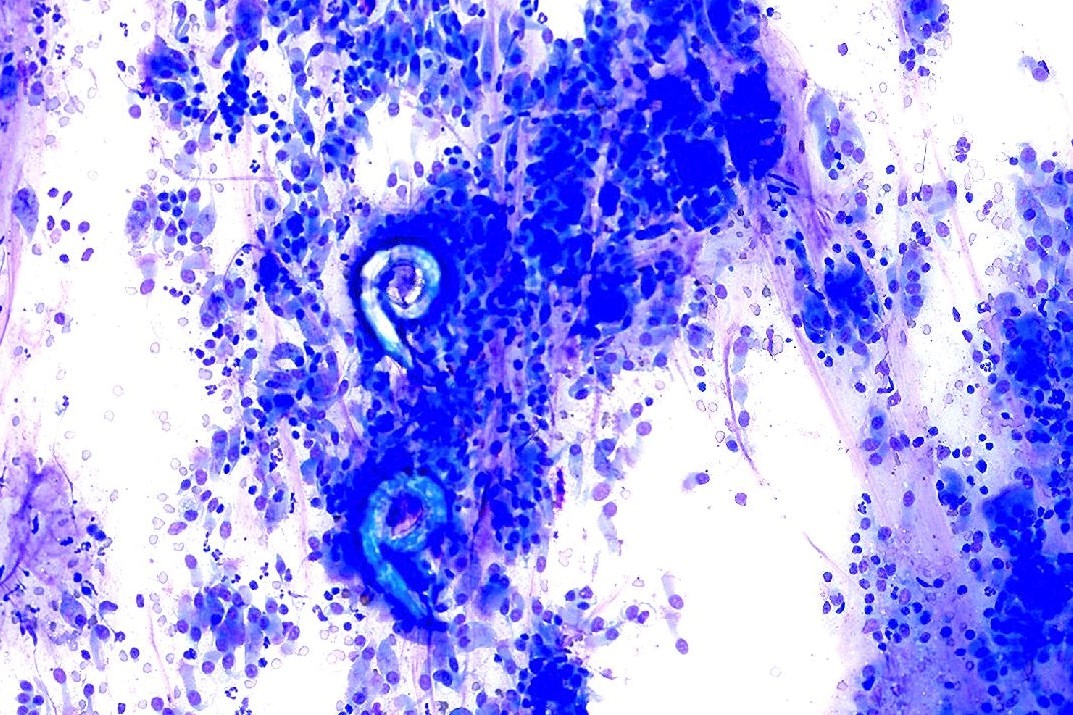

A transoral wash is obtained. A slide prepared for cytologic evaluation is shown: